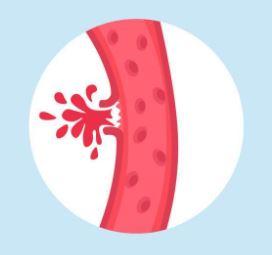

A stroke is when there is not enough blood in the brain. It could be because:

One of the tubes going to the brain tears a little bit and some blood leaks out |

Other ways a stroke can happen are:

- Some of the tubes going to the brain are a bit tangled up so blood gets stuck

- Some of the tubes going to the brain are a bit small and thin so blood gets stuck